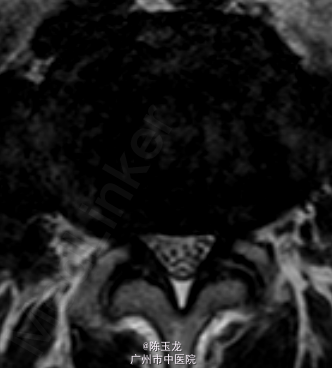

体查:腰椎活动稍受限,腰部有明显叩击痛,左小腿外侧区域感觉减退;双侧直腿抬高试验(—)。 辅助检查:三大常规、血生化、肝肾功能未见明显异常。腰椎MRI示:L4/5椎间盘突出。图片如下。